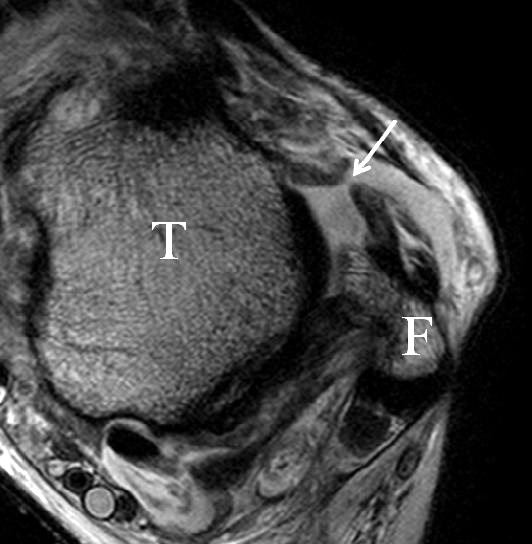

Bezogen auf die Transversalebene verläuft die Syndesmose ca. 30° schräg cranio-caudal anguliert (Abb. 15 a). Häufig lassen sich drei Hauptfaszikel differenzieren: das kürzeste superiore, das stärkste mittlere und das längste kaudale Faserbündel. Ein akzessorisches Bündel, das anteriore-inferiore, tibiofibulare Ligament (AITFL) oder auch Bassett-Ligament wird in 80-94% der Patienten nachgewiesen 8. Dies weist einen unmittelbaren Bezug zur anterolateralen Talusschulter auf (Abb. 17). In Kombination mit einer Außenbandinstabilität und konsekutivem, talarem Vorschub kann dieses zu einem Impingement an der anterolateralen Taluskante führen mit nachfolgender chondraler oder osteochondraler Läsion.